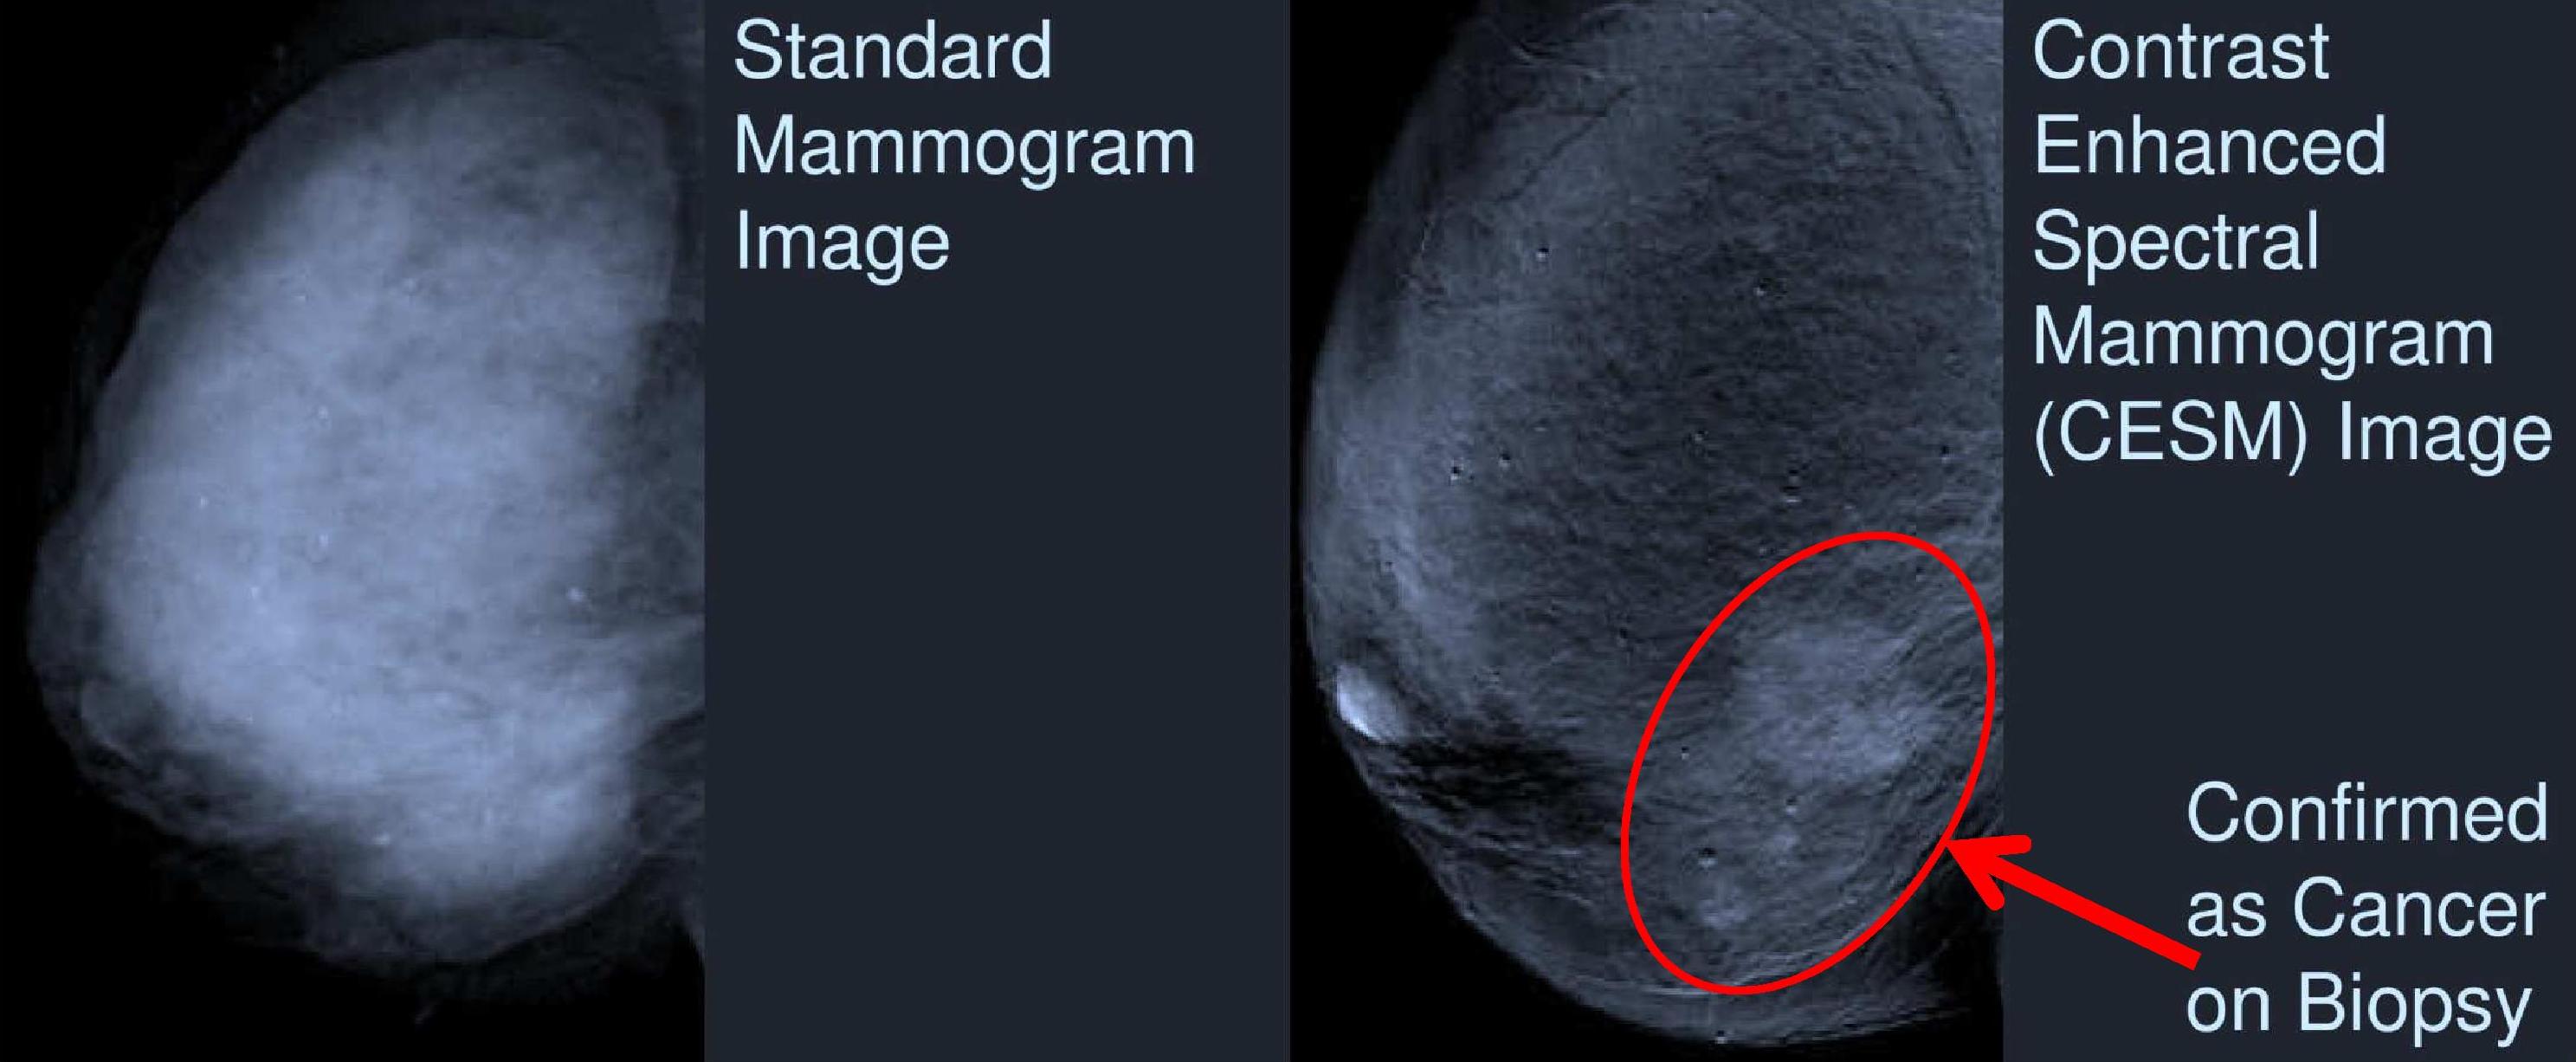

OXNARD, Calif., July 24, 2012 (GLOBE NEWSWIRE) -- Rolling Oaks Radiology, a division of RadNet, Inc. (Nasdaq:RDNT), a national market leader providing high-quality, cost-effective diagnostic imaging...

OXNARD, Calif., July 24, 2012 (GLOBE NEWSWIRE) -- Today DUX Dental announced that Mammograms In Action® will be the recipient of the company's 2012 "Bib-Eze for Boob-Eze" campaign proceeds....